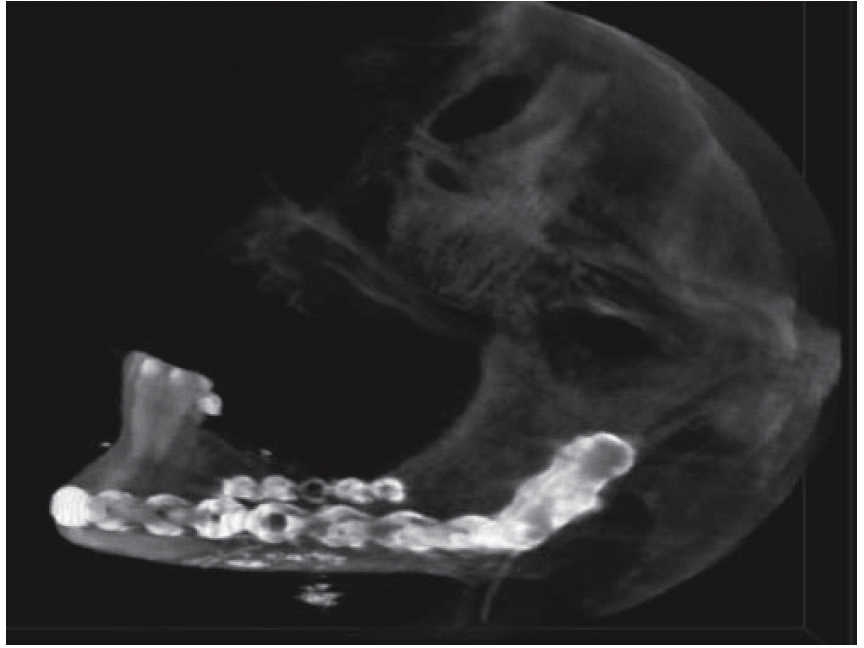

Femenino de 73 años con diagnóstico de fractura de cuerpo mandibular izquierdo por proyectil de arma de fuego (Figura 12). Paciente refiere que es asaltada en la vía pública, le retiran su vehículo y al mostrar resistencia le disparan a dos metros de distancia. Acude a nuestro hospital ocho días posteriores al evento, refiere ingresada previamente en otra casa de salud. A la exploración física presenta zona hiperémica y aumento de volumen en región submandibular izquierda fluctuante. Con orificio de entrada a nivel submandibular izquierdo con presencia de secreción blanca fétida, y orificio de salida a nivel cervical derecho cicatrizado. Intraoralmente edéntula parcial con múltiples focos sépticos en maxilar, en fondo de saco mandibular izquierdo un resto radicular de primer molar en línea de fractura. Movilidad del segmento mandibular importante por fractura de cuerpo que dificulta la deglución.

Se inicia tratamiento terapéutico de inmunización, antibioticoterapia, analgesia, extracción de focos sépticos y lavados mecánicos de la herida. La paciente no cuenta con prótesis ni parcial ni removible por lo que para establecer la relación intermaxilar y altura facial se confeccionan férulas de Gunning (Figura 13). A los diez días del tratamiento inicial se encuentra con adecuada cicatrización a nivel alveolar, con presencia de secreción no fétida a nivel de herida mandibular y se procede a realizar el segundo procedimiento mediante un abordaje extraoral con una placa de reconstrucción mandibular 2.4 y una placa 2.0 para un segmento óseo (Figuras 14 y 15). Se otorga el alta, acude a valoraciones periódicas con buena cicatrización (Figura 16), y adecuada movilidad mandibular. A las tres semanas posteriores a la reconstrucción se indica a la paciente iniciar tratamiento protésico para su rehabilitación.